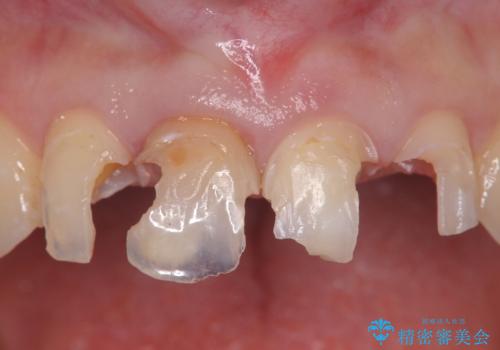

見た目の悪いクラウンをやりかえたい

- 色や形、適合の悪いクラウンの再治療を希望され来院されました。

装着されているクラウンを除去し、自然な色調のジルコニアクラウンによる審美生の改善、インプラントを用いた欠損部の機能回復を計画します。